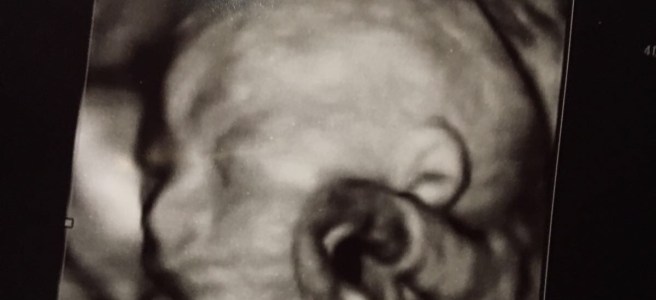

Als ik naar mijn dochter kijk, zie ik de tranen over mijn wangen rollen nadat ik Frances voor het eerst zag. Wat zich vroeger beperkte tot wat schopjes door mama’s buik, liet zich nu in haar volle glorie aanschouwen. Ze is superknap en alles zit erop en eraan. Het voelde of er een kraan met emoties werd opengedraaid terwijl alle loodgieters op een conferentie zaten, in Brazilië. Zelf al meer dan een decennium vaderloos zijn en dan je eigen vlees en bloed vasthouden. Het doet wat met je. Tegen dat ik mijn zuster aan de lijn had, kreeg ik niet veel meer dan ‘ja’ en ‘neen’ door mijn strot geperst.